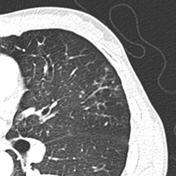

Aeitiology of bronchiectasis include ?